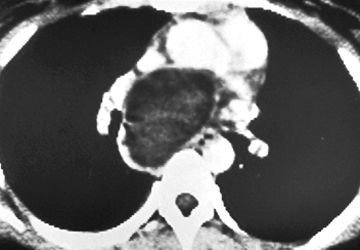

• Bronxial və enterik sistlərin diaqnozu adətən çıxarıldıqdan sonra dəqiqləşir. Perikardial sistlərin diaqnozu görüntüləmə ilə dəqiqləşdirilə bilir (Şəkil 23), lakin diferensiasiya çətinliyi və simptomatik olanlarda cərrahi eksiziya lazım gəlir.

Şəkil 23. KT. Perikardial sist